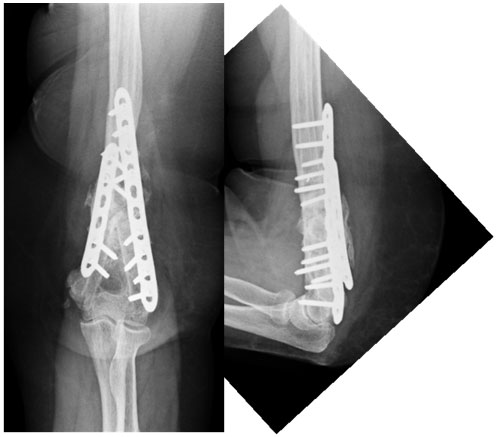

2 days post surgery

The broken and loose implants were removed, the fracture ends were freshened and fixation of both the medial and lateral pillars was done using locked plates. The movements of elbow 2 days after surgery.

6 months post surgery

The fracture healed well without any complications or bone grafting.